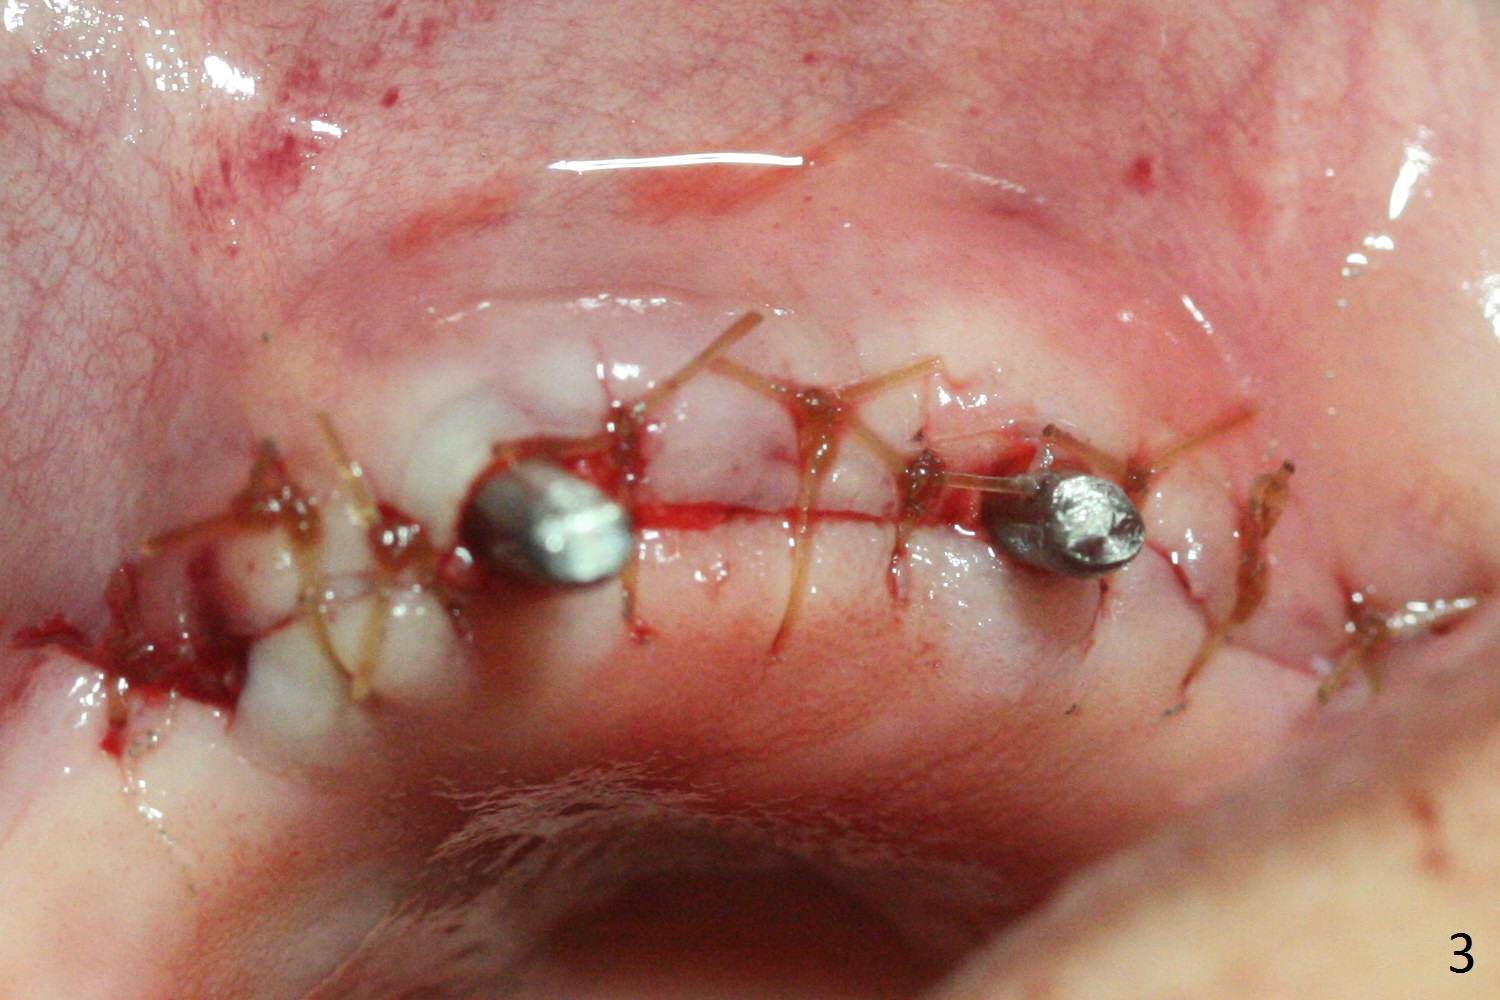

Incision reveals that the ridge at #9 and 11 is narrower than expected. A 3x14 mm 15º 1 piece implant is placed at the site of #9, while a 3x17 mm straight 1-piece one is placed at #11 (Fig.1,4). Insertion torques at #9 and 11 are 20 and 30 Ncm, respectively. The relatively low insertion torque is partially due to osteoporosis. The 65-year-old lady also has dry mouth. Osteotomy should be underprep. The position and trajectory of the implants are dictated by the partial denture (Fig.2). After minor abutment adjustment (Fig.3), an immediate provisional bridge is fabricated. There is no interference when the partial is removed and inserted. After bone graft (Fig.4 ^) and Osteogen Membrane, the ridge (Fig.3) is wider than before. The patient returns for reline 2 months postop (Fig.5-7). In spite of insufficient oral hygiene, the gingiva remains healthy around the implants. To form distinct papillae, acrylic should be added to (Fig.8 yellow line) and removed from (hushed area) the individual provisional crowns. One month after provisional modification (Fig.10, as compared to Fig.5), the pontic recipient site is concave (Fig.11) and becomes less concave after cord packing and abutment trimming. When the provisional bridge is reseated after impression (Fig.12), the pontic recipient site must be blanched again. Please trim the pontic recipient site of the model ~ .5 mm to enhance cosmetics. Water Pik has been used since surgery, but it may be related to loss of bone graft 3.5 months postop (Fig.9 *). One month post cementation, the patient has complained of pain when water pik is irrigating the gingiva palatal to the FPD, apparently in association with denture-related Candidiasis. Two weeks of use of Mycostatin Oral Suspension, peri-implantitis or peri-implant mucositis-like signs and symptoms disappear (Fig.13). CBCT taken 6 months postop confirms that the implants appear to be have been placed in the bone (14,15). The FPD appears to be loose 2.5 years post cementation.